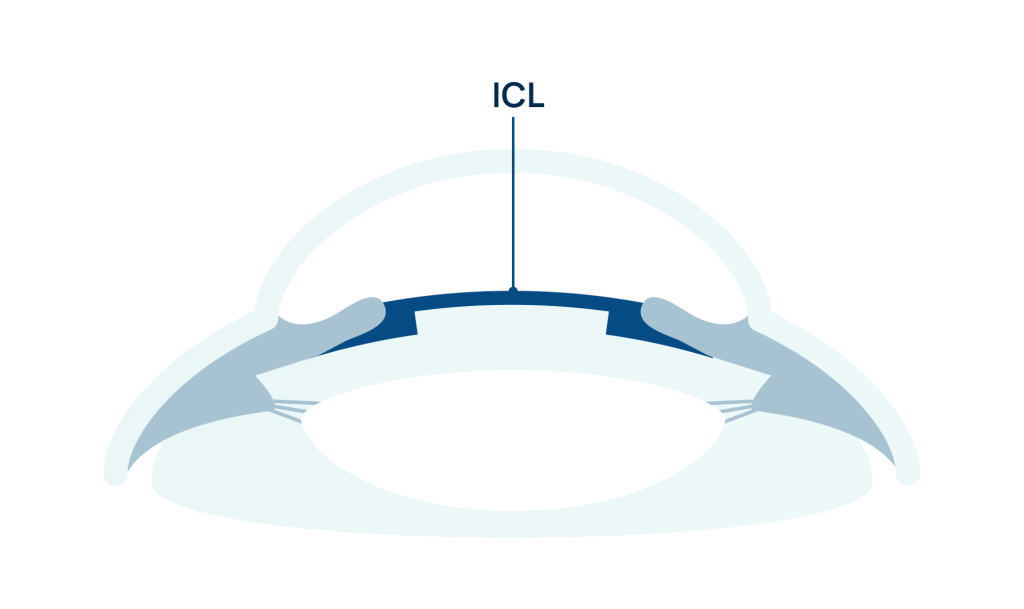

Questa tecnica prevede l’inserimento di una lente speciale, personalizzata sulle esigenze del paziente, tra il cristallino e l’iride, senza rimuovere o danneggiare alcuna parte dell’occhio.

È definita ‘lente fachica’, perché la lente non sostituisce il cristallino, a differenza delle lenti utilizzate nella chirurgia della cataratta, ma si colloca a pochi micron da esso senza danneggiarlo.

L’impianto di lenti ICL (Implantable Collamer Lenses) è una procedura chirurgica che impianta una lente all’interno dell’occhio per correggere difetti visivi come miopia, ipermetropia e astigmatismo elevati. A differenza della chirurgia laser, le ICL non richiedono la rimozione di tessuti oculari, ma vengono inserite tra l’iride e il cristallino, migliorando la vista senza alterare permanentemente l’occhio.